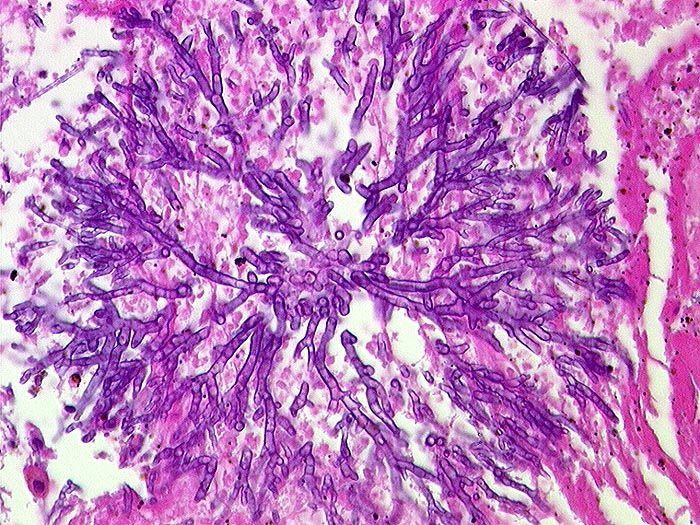

Einleitung

Aspergillen gehören in die Gruppe der Schimmelpilze und wachsen ubiquitär auf organischen Stoffen. Der Erreger ist charakterisiert durch echte septierte Hyphen von 3 bis 6 Mikrometer Durchmesser. Die Hyphen verzweigen sich in einem Winkel von 45 Grad. Selten sind auch die (> 10851) (> 10849) Fruchtköpfe (Conidiophoren) nachweisbar. Aspergillusinfekte manifestieren sich je nach Resistenzlage als Aspergillom, invasive Aspergillose oder allergische Aspergillose. Der Nachweis von Aspergillus beweist noch nicht eine klinisch relevante Infektion.